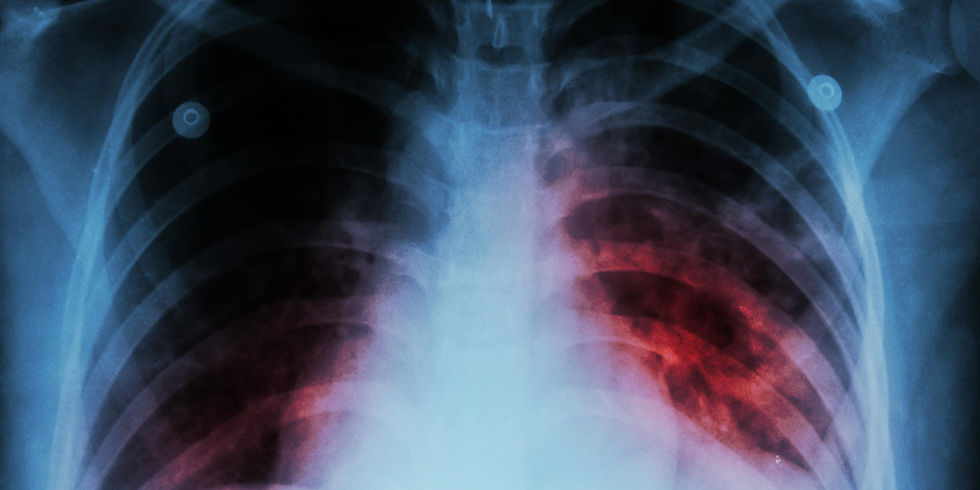

La secretaria de salud hizo un llamado a la población para prevenir la tuberculosis, una enfermedad infecciosa que afecta principalmente los pulmones, pero también puede dañar otros órganos como los ganglios, el cerebro, los riñones y los huesos.

En las unidades médicas de Salamanca se realizan pruebas para detectar la enfermedad, como análisis de laboratorio, radiografías y valoraciones clínicas.